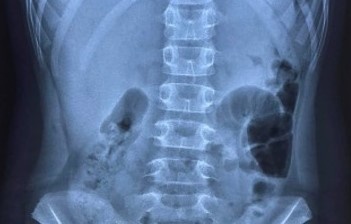

UTI có thể ảnh hưởng đến bất kỳ bộ phận nào của hệ tiết niệu như thận, niệu quản, bàng quang và niệu đạo. Hầu hết nhiễm trùng liên quan đường tiết niệu dưới là bàng quang và niệu đạo.

Nhiễm trùng ở bàng quang gây đau đớn và khó chịu. Trong trường hợp nghiêm trọng, nó có thể lây lan đến thận.

UTI chủ yếu do các vấn đề về vệ sinh, hoạt động tình dục, dùng loại thuốc tránh thai và cũng có thể do mãn kinh. Ảnh: Kahs.